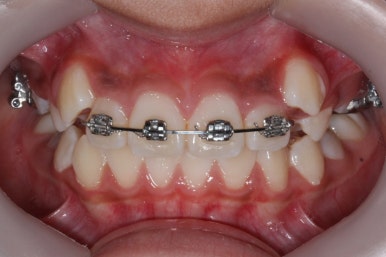

4개월이 지난 모습입니다.

송곳니가 덧니처럼 있었는데 아무것도 안해줬음에도 가지런한 느낌이 훨씬 좋아졌습니다.

공간이 생긴 송곳니는 편안한 위치로 좀 더 서서히 이동을 합니다.

4개월만에 유치가 빠지고 영구치가 조금씩 맹출이 되고 있는 것을 볼 수 있습니다.